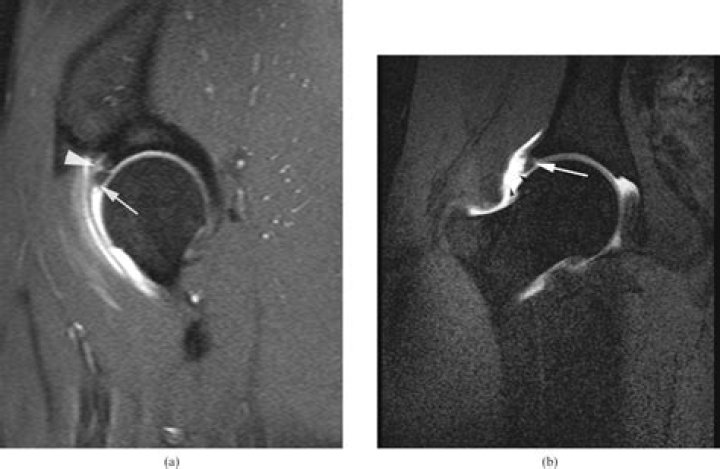

An arthrogram is a test that helps healthcare providers diagnose joint problems, such as hip or shoulder pain. MR arthrograms can show ligament, tendon and